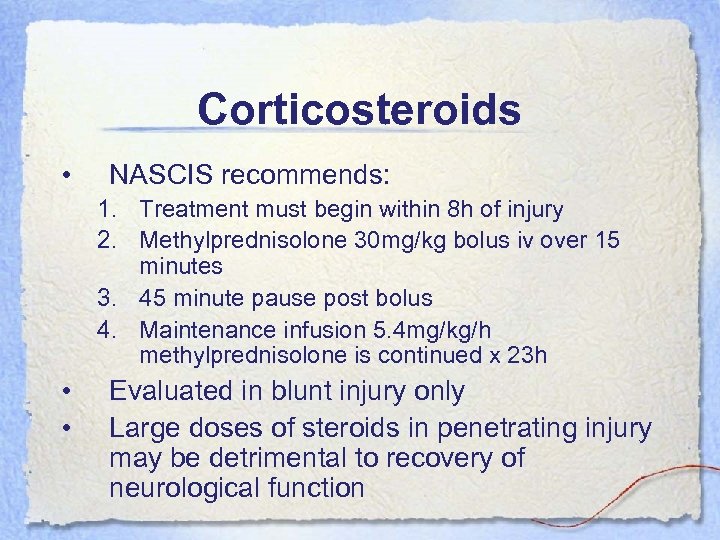

Corticosteroids • NASCIS recommends: 1. Treatment must begin within 8 h of injury 2. Methylprednisolone 30 mg/kg bolus iv over 15 minutes 3. 45 minute pause post bolus 4. Maintenance infusion 5. 4 mg/kg/h methylprednisolone is continued x 23 h • • Evaluated in blunt injury only Large doses of steroids in penetrating injury may be detrimental to recovery of neurological function

Corticosteroids • NASCIS recommends: 1. Treatment must begin within 8 h of injury 2. Methylprednisolone 30 mg/kg bolus iv over 15 minutes 3. 45 minute pause post bolus 4. Maintenance infusion 5. 4 mg/kg/h methylprednisolone is continued x 23 h • • Evaluated in blunt injury only Large doses of steroids in penetrating injury may be detrimental to recovery of neurological function